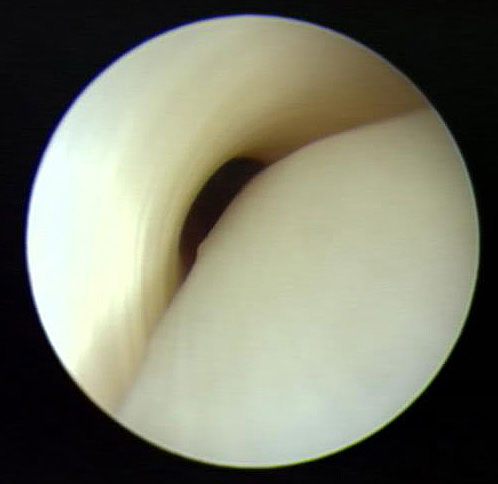

Ggf. ergänzendes MRT zur Beurteilung des Knorpels im unteren Sprunggelenk bei V.a. Arthrose. Bei Pes planovalgus Beurteilung der Tibialis posterior Sehne, bei Pes cavus der Peronealsehnen.

3. Alternativ ist eine Transposition der Sehne des M. flexor digitorum longus auf das Os naviculare möglich (FDL-Transfer). Das tendoskopische Debridement bietet sich insbesondere an bei Patienten mit im MRT noch weitgehend intakter Sehne (Abb. 21)."> 3. Alternativ ist eine Transposition der Sehne des M. flexor digitorum longus auf das Os naviculare möglich (FDL-Transfer). Das tendoskopische Debridement bietet sich insbesondere an bei Patienten mit im MRT noch weitgehend intakter Sehne (Abb. 21)." srcset="/assets/images/x/20-4wazvyk6qcpt2xs.jpg 1x, /assets/images/y/20-a6v6m55vtx2zmry.jpg 1.5x, /assets/images/q/20-ye4s9jha1jrvcge.jpg 2x" width="270" height="240" loading="lazy">

Abbildung 20

3. Alternativ ist eine Transposition der Sehne des M. flexor digitorum longus auf das Os naviculare möglich (FDL-Transfer). Das tendoskopische Debridement bietet sich insbesondere an bei Patienten mit im MRT noch weitgehend intakter Sehne (Abb. 21)."> 3. Alternativ ist eine Transposition der Sehne des M. flexor digitorum longus auf das Os naviculare möglich (FDL-Transfer). Das tendoskopische Debridement bietet sich insbesondere an bei Patienten mit im MRT noch weitgehend intakter Sehne (Abb. 21)." srcset="/assets/images/0/21-n45853s2pe0a6dv.jpg 1x, /assets/images/w/21-rjh7v27n1j3bg4x.jpg 1.5x, /assets/images/w/21-7spvf34wgeytm3k.jpg 1.844x" width="270" height="240" loading="lazy">

Abbildung 21